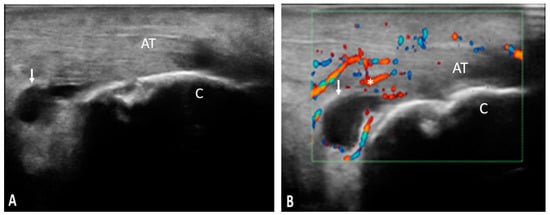

Figure 3. AT—Achilles tendon; C—calcaneus; ↓—calcaneus erosion; pathology—longitudinal (A) and transverse scan (B) in grey-scale of the Achilles tendon showing erosions in two perpendicular planes.

The Achilles tendon was the most frequently involved in the inflammatory process both from the clinical and ultrasonographic point of view. Taking into account the characteristics evaluated by ultrasound, 42 of the examined Achilles tendons presented the following inflammatory changes: thickening (90.47%), hypoechogenicity (90.47%), loss of fibrillary pattern (90.47%), enthesophytes (76.19%), calcifications (66.66%), erosions (66.66%), power Doppler signal (28.57%), retrocalcaneal bursitis (28.57%), and retroachilles bursitis (23.80%) (Figure 5).